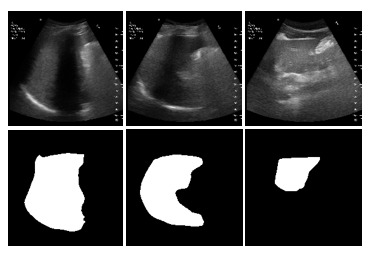

US Liver Segmentation Results: We used FCN [10], UNet [13], UNet++ [20] with EfficientNetB7 encoder, and TransUNet [2] for segmenting US scans for US liver segmentation (Table 1). TransUNet achieved the best Accuracy (Acc.), Dice Score Coefficient (DSC), Intersection over Union (IoU), and Hausdorff distance (HD) for unseen data. This is because TransUNet uses transformers to encode tokenized image patches from a CNN feature map. Thus, the input sequence captures global contexts [2]. We used UNet as the decoder to decode the hidden feature for generating the final segmentation masks. 2D liver predictions overlap well with ground truth liver labels. This, in turn, leads to an accurate liver volume calculation. Ours is the first method that uses a transformer network in US liver segmentation. Following this result, we used TransUNet for all other experiments.

Figure 2: US segmentation and 3D reconstruction results: Three input US sagittal plane images, corresponding segmentations, and 3D liver reconstructions using the shape parameters for three subjects.

Table 1: Segmentation accuracy: TransUNet performs better and, hence, was selected for subsequent experiments. \ast represents the usage of EfficientNet-B7 as an encoder. 3D reconstruction accuracy: CD and MSD are less when we combine TransUNet with Param. Regress. MLP than UNet.

Segmentation FCN UNet UNet++\ast TransUNet

Acc. (%) \uparrow 93.2 95.4 94.4 97.5

DSC (%) \uparrow 38.5 65.6 68.1 91.3

HD (mm) \downarrow 5.5 4.8 4.5 3.6

IoU (%) \uparrow 24.1 50.2 52.7 84.4

Recon. TransUNet UNet

Accuracy + Recon. + Recon.

MSD (mm)\downarrow 6.6 6.8

CD (mm) \downarrow 12.8 13.1